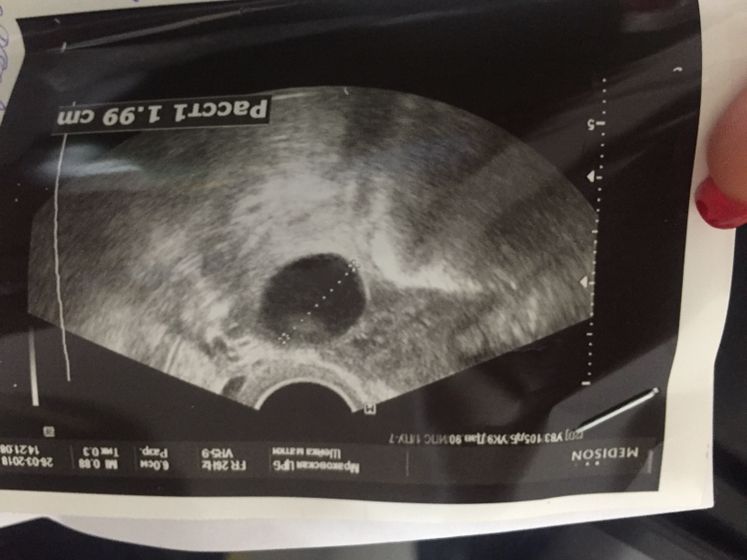

В левом яичнике мой дф подрос до 19.9мм

Эндометрий 9 мм